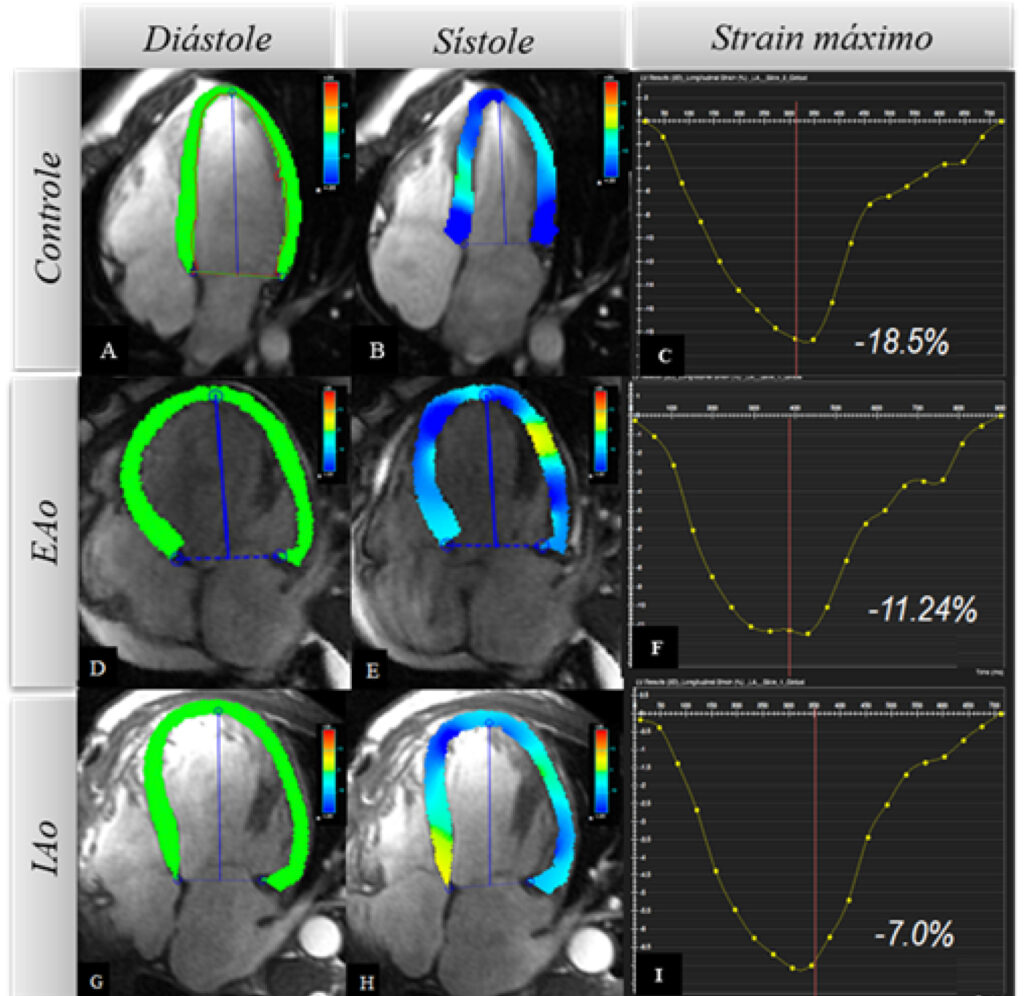

Incluímos 44 participantes (26 valvopatas aórticos/١٩ controles). O strain longitudinal global utilizou software específico (Circle Cardiovascular Imaging 42) e o deslocamento linear longitudinal apenas medidas lineares de distância entre a base e o ápex do ventrículo esquerdo, gerando deslocamento máximo, velocidade máxima no início da diástole, velocidade na diástase e a relação entre velocidade na diástase e velocidade máxima no início da diástole.

Resultados

Deslocamento máximo e velocidade máxima no início da diástole correlacionaram-se com strain longitudinal global (r=0,69 e r=0,65 respectivamente) e com a fração de ejeção do ventrículo esquerdo (r=0,47 e r=0,57, p<0,001 para ambos). Deslocamento máximo e velocidade máxima no início da diástole apresentaram área sob a curva Característica de Operação do Receptor de 0,88 e 0,91 e, no melhor ponto de corte (-0,13 e 0,66), sensibilidade de 72,43% e 57,14% e especificidade 80,65% e 87,10%, respectivamente, quando comparados ao strain longitudinal global. Utilizando a fração de ejeção do ventrículo esquerdo como referência, foram obtidos 0,70 e 0,82, e, no melhor ponto de corte (-0,11 e 0,61), sensibilidade de 75,00% e 50,00% e especificidade 72,97% e 78,38%, respectivamente.